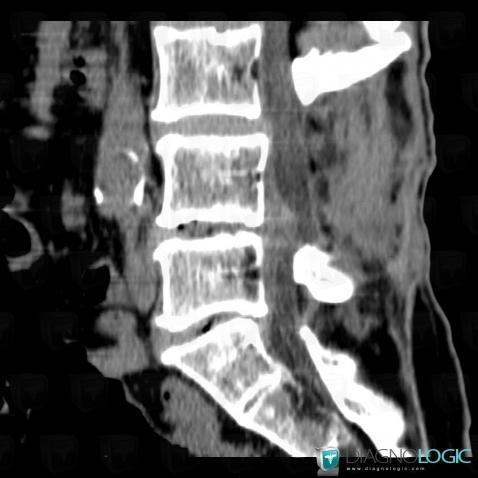

Degenerative disk disease, Vertebral body / Disk, CT

Here is the specific information in the key image above:

- Diagnosis Herniated disc, Location(s) Vertebral body / Disk, with gamuts Spinal disc lesion

- Diagnosis Degenerative disk disease, Location(s) Vertebral body / Disk, with gamuts Discal / Intraverbetral gaz